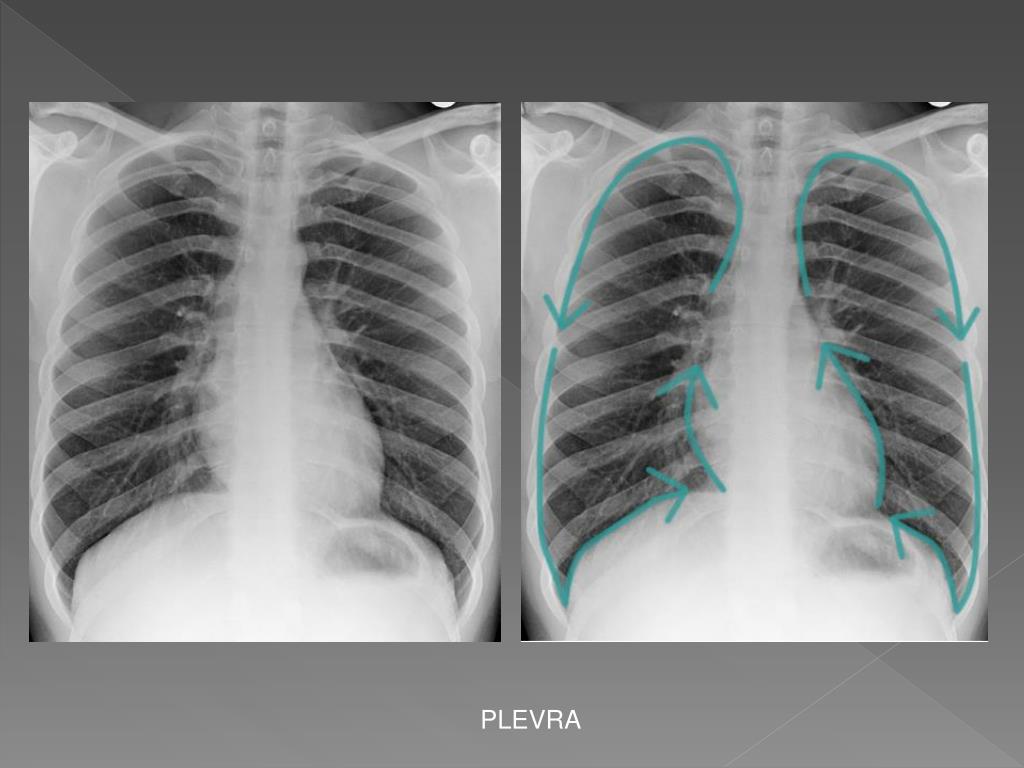

28. SAĞ PARATRAKEAL ÇİZGİ

36. PLEVRA